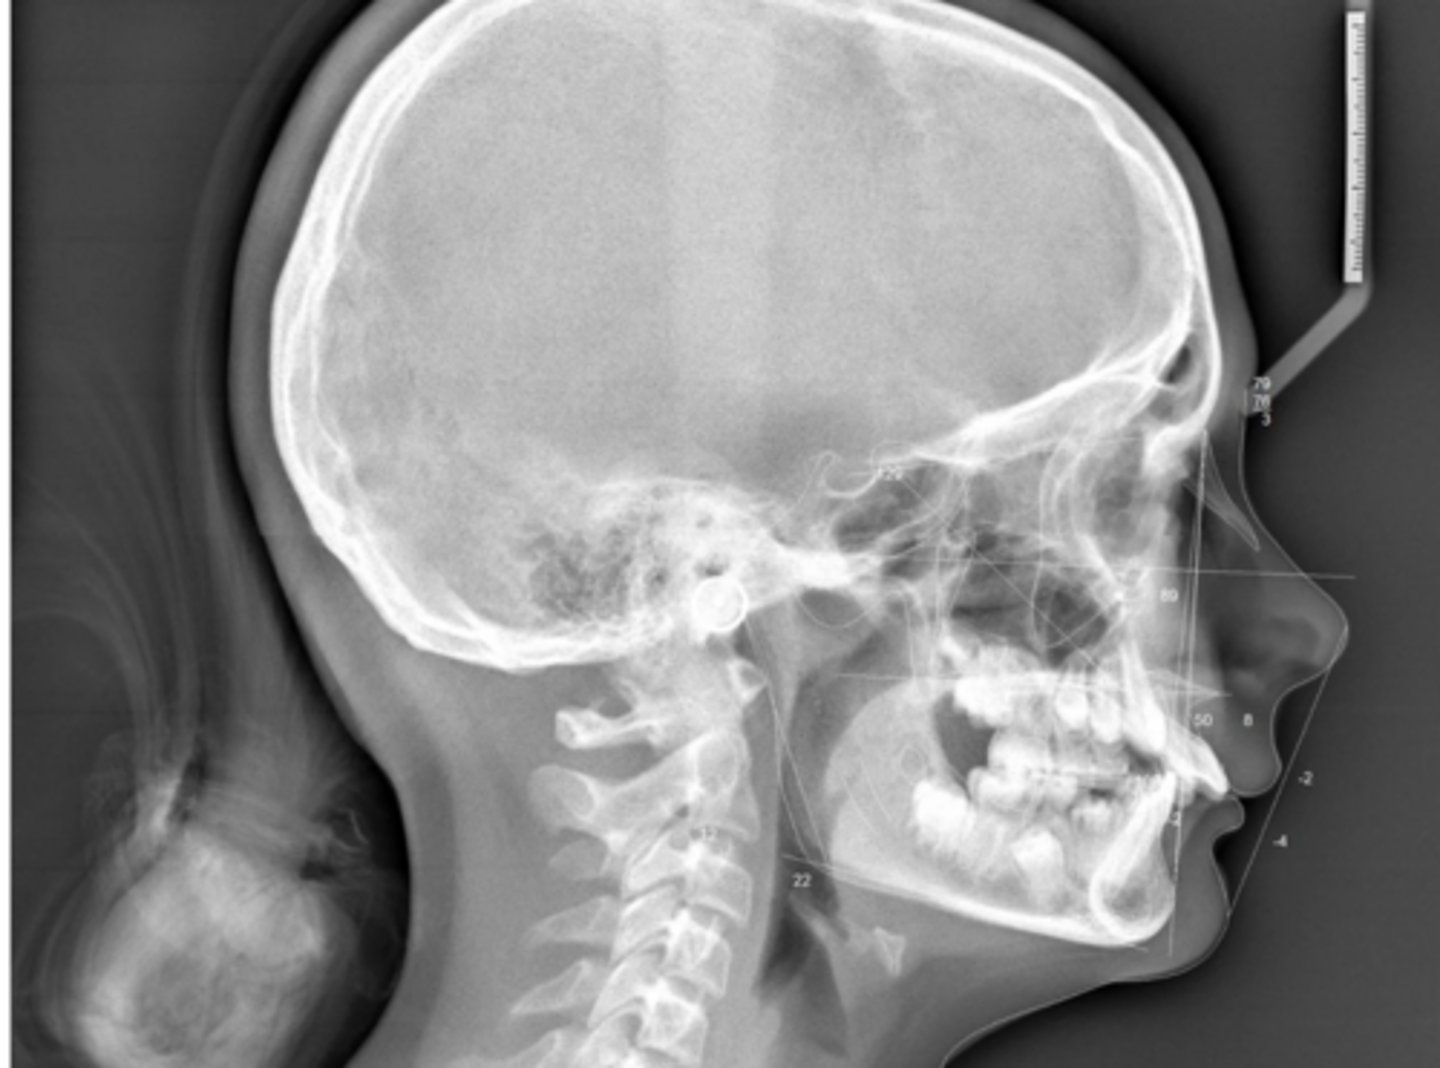

Class II skeletal (very light)

What type of skeletal malocclusion is this patient?

Hypodivergent

Are the hyper-, hypo-, o normo- divergent?

proclined

Maxillary incisors are?

Class II

Hyperdivergent

Class I

Normodivergent

No

Are the maxillary incisors proclined/flared?